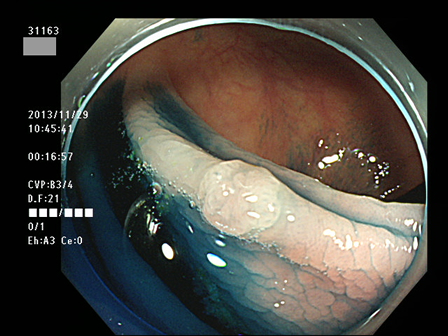

上記100名より抽出した平坦・陥凹型腺腫(=癌化の危険が高いが見落としやすい病変)の内視鏡写真